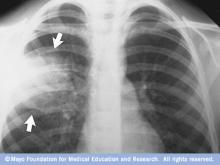

X-ray image of lungs with pneumonia

Chest X-ray showing pneumonia

This chest X-ray shows an area of lung inflammation indicating the presence of pneumonia.

• Chest X-ray. This helps your doctor diagnose pneumonia and determine the extent and location of the infection. However, it can't tell your doctor what kind of germ is causing the pneumonia.